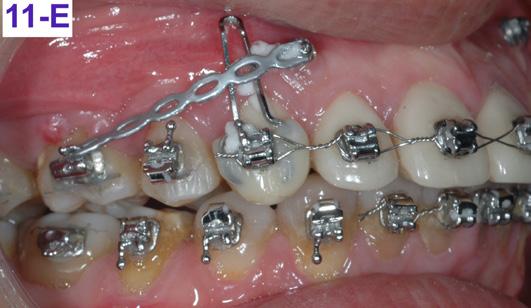

The brackets were bonded on the maxillary incisors and there was a progression of the arch wires a .014 NiTi, a .016 SS and a .018 SS. The progression of the arch wires in the mandible was a .016 NiTi, a .016 SS, a .018 SS and a .018 x 025 SS with the step-down distally to the cuspids. A 1.6 x 8.0 mm Ancor Pro TADs were inserted on the buccal aspect distally to the maxillary lateral incisors to aid the intrusion of the maxillary anterior sextant.8 Maxillary incisors were laced back, to prevent splaying during the intrusion and two links of an elastomeric chain were attached from the TADs to the arch wire. Power arms were bent from a .016 x 022 SS wire and ligature tied to the bracket #13(6) an #24(12).

Closing coil springs were attached from TADs to the power arms. To prevent an undesirable labial moment (flaring) of the maxillary incisors, Class I (labial intra) elastics (¼” – 4.5 oz) were

placed from the buccal hook of the maxillary first molar to the helical loop on the arch wire. The helical loop was fabricated just distally to the maxillary lateral incisors on a. 018 SS arch wire (Figure 8-D, E, F, G).

After re-bracketing, the treatment continued with the progression of the arch wires: a .014 NiTi, a .018 NiTi, a .019x025 “V” Force -3 and the final arch wire a .018x.025 SS. These final arch wires were left for three months. After this time, the esthetics, TMJ, airway, occlusion and alignment were evaluated. The patient reported that he was satisfied, and very happy with the result (Figure 11-A, B, C, D, E, F).9